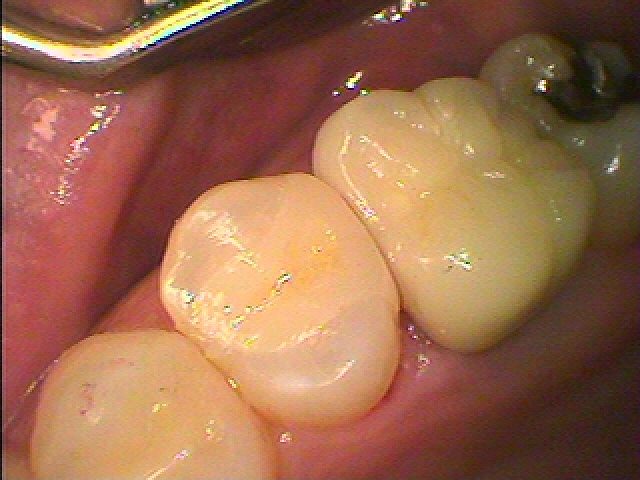

白いセラミック治療になりました。| |広島市安佐南区の歯科医院 白いセラミック治療になりました。 トップ お知らせ・ブログ 白いセラミック治療になりました。 白いセラミック治療になりました。 Web診療予約 初めての方へ 選ばれ続ける理由 院内設備について 歯が痛いしみる一般歯科 歯がぐらぐらする歯周病 健康な歯を保ちたい予防歯科 子供の虫歯予防をしたい小児歯科 銀歯をセラミックに審美歯科 白い歯を目指しませんか?ホワイトニング 矯正専門医がいるので安心矯正歯科 抜けた歯を補いたいインプラント・入れ歯 医院案内 スタッフ紹介 メリィハウス歯科クリニックオフィシャルホームページ ラベンダー歯科クリニックオフィシャルホームページ お知らせ・ブログ ホーム 診療科目 一般歯科 歯周病治療 予防治療 小児歯科 審美治療 ホワイトニング 矯正歯科 入れ歯・インプラント マウスピース矯正 初めての方へ 院長・スタッフ 設備紹介 医院案内・アクセス メニューを閉じる